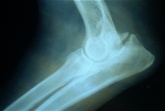

El primer paso en el diagnóstico es el examen clínico por un veterinario. Si se sospecha la displasia del codo, se realizan radiografías. La posición más comúnmente usada es la imagen lateral de la articulación con una flexión de 45º. Esta forma permite ver la apófisis ancónea y la congruencia general de la articulación con la aparición o no de artrosis.

El fragmento de la apófisis coronoides puede no ser visible como en la RX siguiente, y se hace necesario siguiendo los signos clínicos, la realización de una artroscopia.

La edad para los diagnósticos de rutina es a los 12 meses. Pero las radiografías de control si se presenta dolor o claudicación pueden realizarse a cualquier edad. Ambas articulaciones deben ser radiografiadas. La proyección medio lateral, se hace con el codo flexionado 45º lo que da buena imagen general, pero superposición de los cóndilos del húmero. Puede hacerse una vista adicional cráneo caudal para poder observar los márgenes laterales de la articulación. Las RX se identifican con el número de pedigree del animal, fecha y profesional actuante.